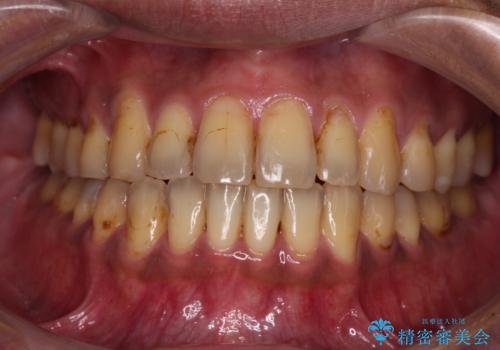

- 前歯の著しい叢生と前突感を気にして来院された患者様です。

叢生が強いため、事前に前歯をワイヤー矯正で速やかに叢生を解消し、その後はインビザラインにて矯正治療を行うこととしました。

ワイヤー矯正を併用したことで前歯の叢生を速やかに解消することができました。

一方口元の突出感を改善するために時間がかかり、2年超を要しましたが、満足のいく仕上がりとなりました。